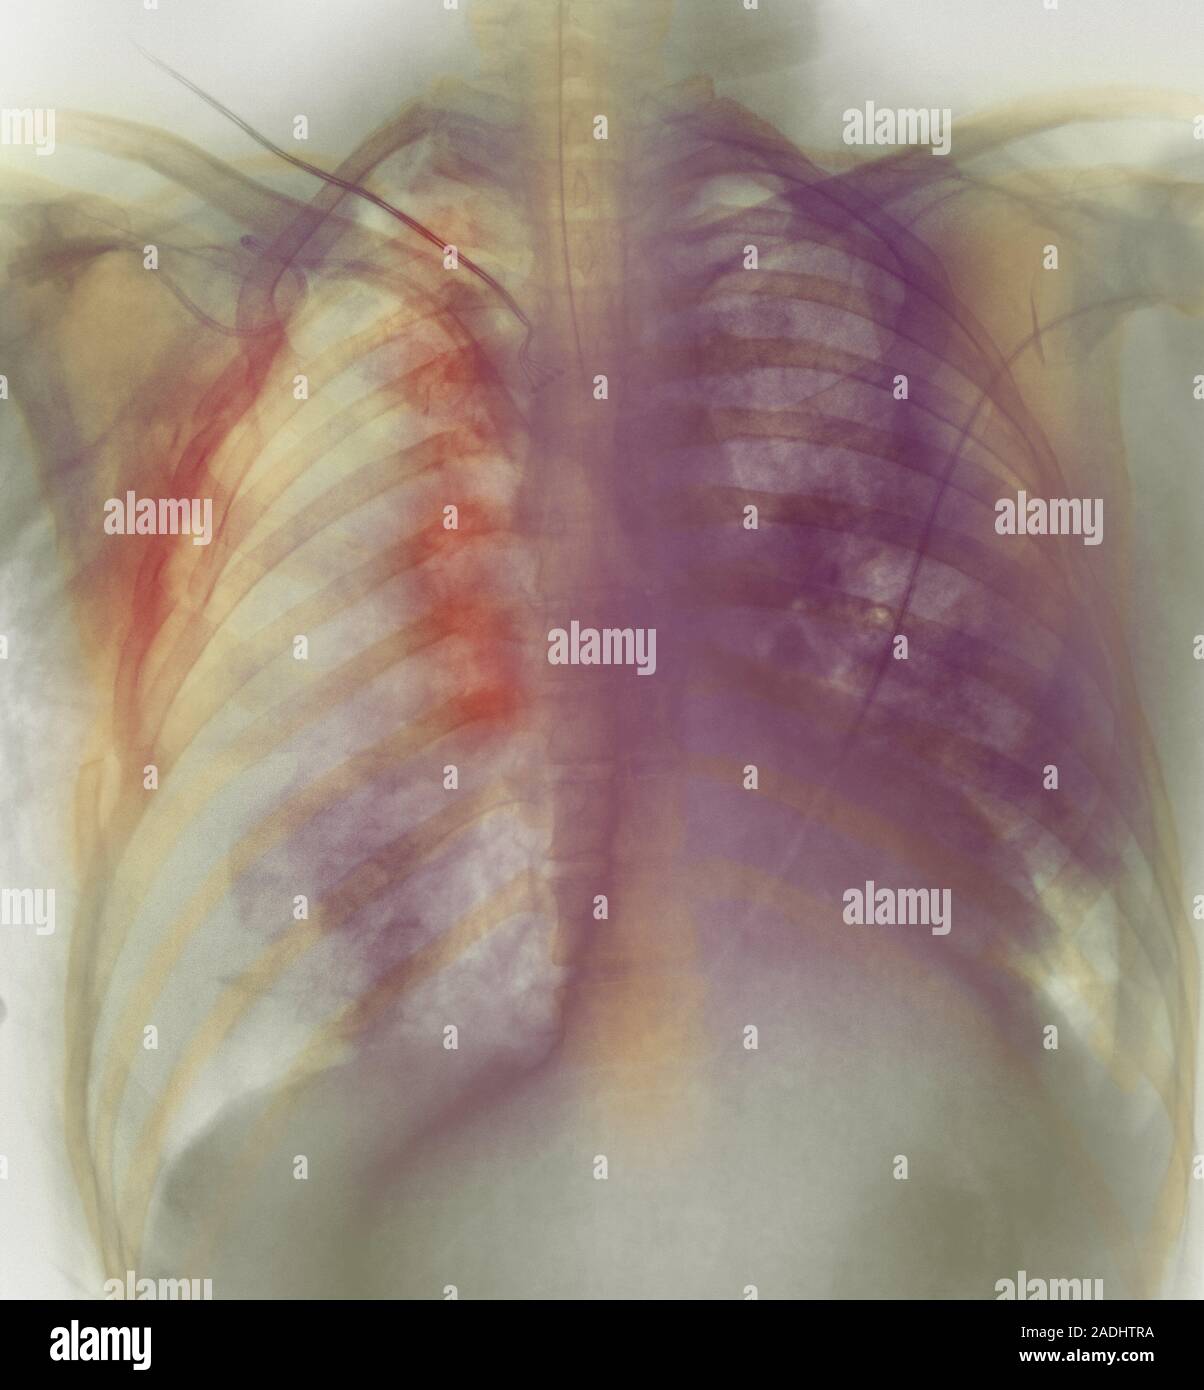

Gebrochene Rippen Wie Lange . Gebrochene Rippen. Farbige Chest XRay zeigt mehrere gebrochene Rippen (orange), unten Mitte Durch eine gebrochene Rippe kann es jedoch zu einer Lungenverletzung kommen Nach und nach verknöchert der Bruch dann aber stabil

Source: lscarecno.pages.dev Gebrochene Rippen. Farbige Chest XRay zeigt mehrere gebrochene Rippen (orange), unten Mitte , Wie lange die Heilung bei einem Rippenbruch dauert, hängt unter anderem von der Art des Bruchs ab ob eine oder merhere Rippen gebrochen sind oder ob die Rippe nur angebrochen war.